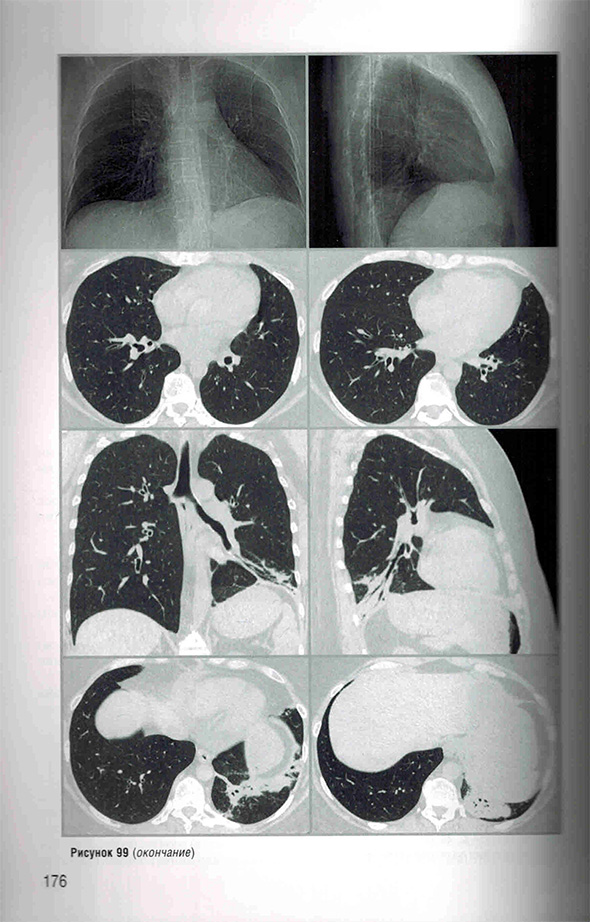

Протокол «ФБЛ (постковидные изменения)»